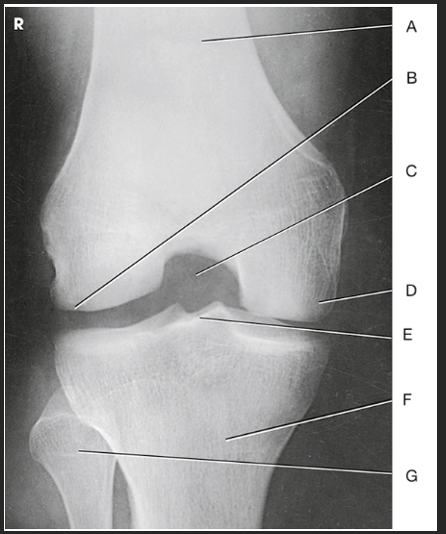

Name this projection.

AP oblique lateral rotation

What is demonstrated?

Medial aspect (distal femur, patella, medial tibial condyles, and fibula)

Label the image: A

femur

Label the image: B

patella

Label the image: C

medial femoral condyle

Label the image: D

lateral femoral condyle

Label the image: E

Lateral tibial plateau

Label the image: F

medial tibial plateau

Label the image: G

medial tibial condyle

Label the image: H

fibula

Label the image: I

tibia